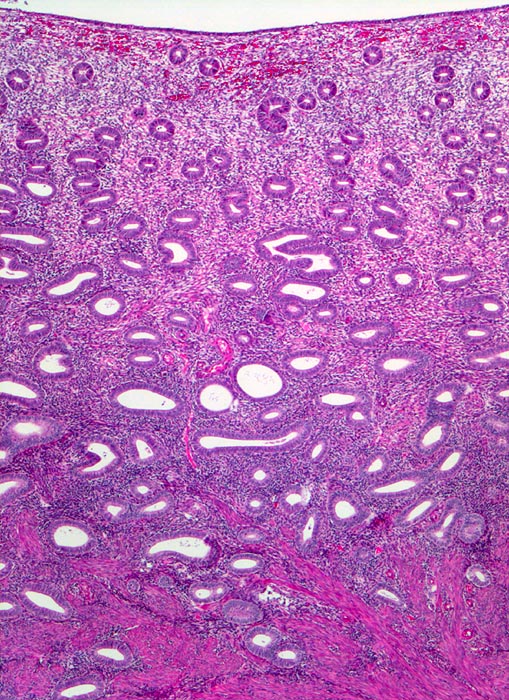

• Stellenweise unscharfe Begrenzung des Sarkoms zum nicht neoplastischen Myometrium (Fragment oben rechts).

• Die spindeligen Tumorzellen mit längsovalen Kernen und reichlich kräftig eosinophilem Zytoplasma bilden Faszikel ähnlich wie nicht neoplastische glatte Muskulatur.

• Tumornekrosen.

• Bereits in der Übersicht (10x) erkennbare diffuse signifikante Zellatypien.